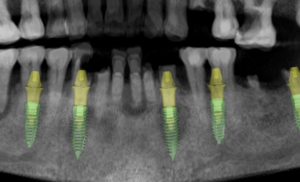

6.2 Inserción del implante

- Colocar el implante a través de la guía si el sistema lo permite, o retirar la guía si la inserción es libre.

- Verificar el torque de inserción y la estabilidad primaria.

6.3 Comprobación final

- Asegurar que el implante tiene la posición tridimensional exacta según el plan digital.

- Colocar los pilares transepiteliales si procede (por ejemplo, AXA).

- Realizar fotografías o escaneado intraoral para documentar el caso y avanzar hacia la fase protésica.